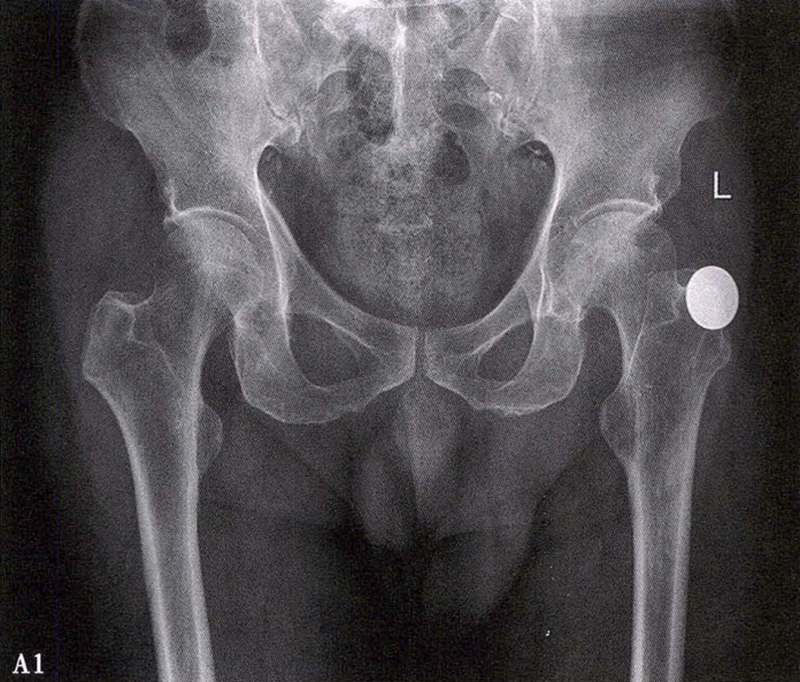

(1)X线检查 X线是诊断股骨头坏死的首选检查手段,常规拍摄髋关节正侧位片。早期股骨头坏死X线片可正常或显示股骨头外上方骨小梁稀疏;病情进展后逐渐出现密度增高、硬化带、囊性变等;晚期则出现股骨头塌陷、关节间隙变窄、Shenton's线不连续、骨关节炎改变等。硬化带和新月征是股骨头坏死X线特征性表现。在股骨头关节面塌陷变形早期上关节间隙不变或增宽后期随着骨关节炎加重关节间隙逐渐狭窄。

X线检查示右侧股骨头骨质密度不均匀

A.男性,71岁,双侧股骨头坏死,右侧Ⅰ期、左侧Ⅲ期。X线片示双侧股骨头形态可,右股骨头未见明显密度改变,左股骨头关节面下见局限性骨密度减低及增高区(A1)。MRI(T2加权像)示右股骨头内双线征,左侧不规则形混杂信号,坏死区远端骨髓水肿(A2、A3)。